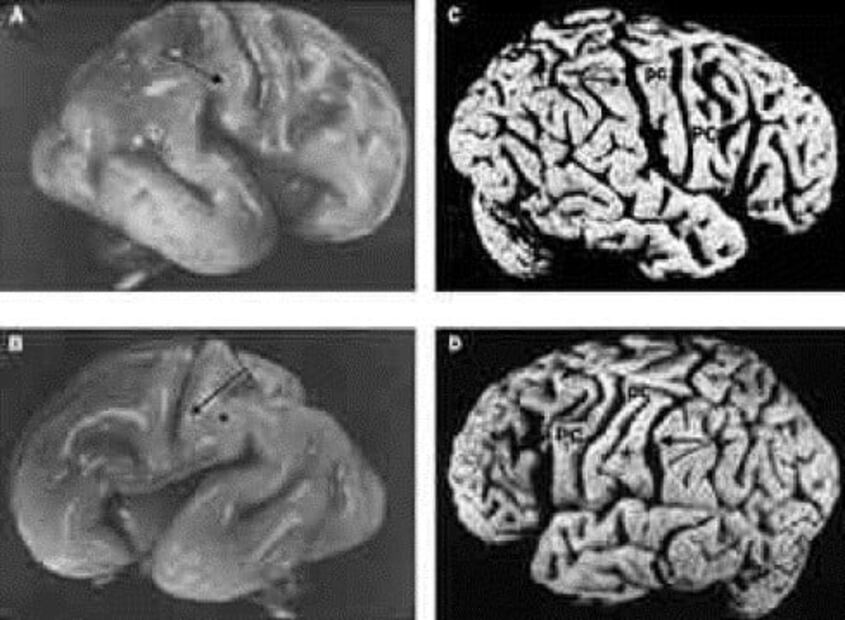

Los investigadores que han examinado el cerebro del genio han llegado a la conclusión de que no es normal. Aunque el cerebro de Einstein pesa un poco menos que el de una persona promedio, la región parietal inferior es un 15% más grande que en un cerebro promedio . Algunos científicos piensan que el cerebro carece de una hendidura llamada cisura de Silvio .

Por lo tanto, algunos neurocientíficos señalan que estas características podrían explicar las habilidades de razonamiento matemático y espacial de Albert Einstein . Además, el cerebro de Einstein no presenta los cambios degenerativos que usualmente estarían presentes en una persona de 76 años de edad. A pesar de estos hallazgos, aún se desconoce exactamente por qué Einstein era un genio.